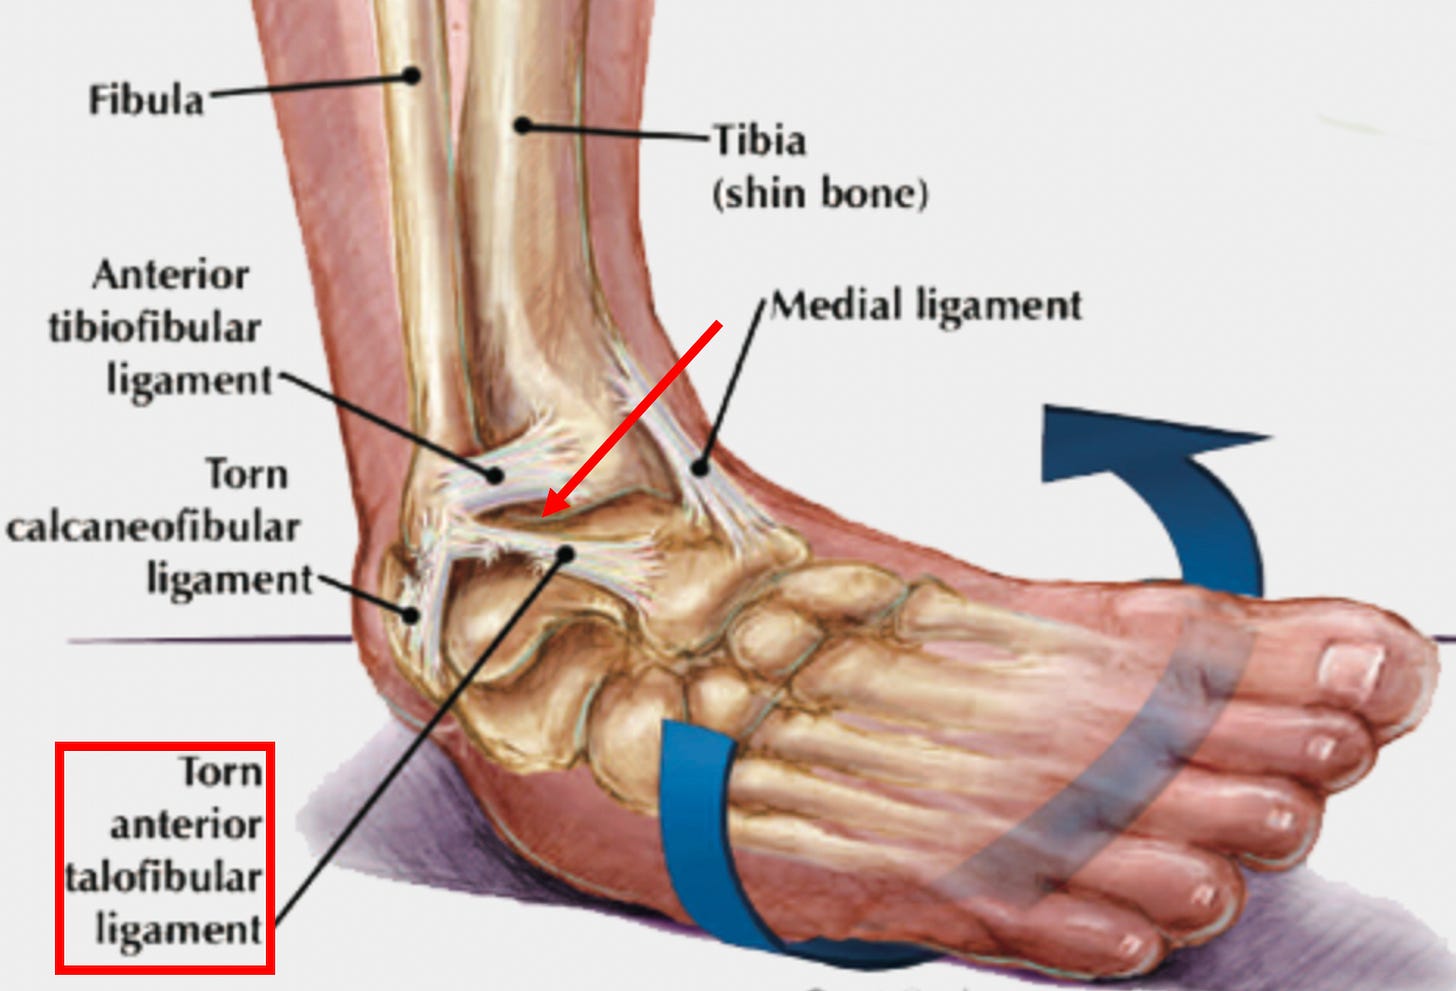

Ligamentous weakness is frequently caused by a chronic injury to a ligament (or an injury which did not properly heal). For example, when the ankle is injured from a sprain, the ligament that keeps the ankle from turning inwards gets damaged, predisposing us to an unstable ankle and future ankle injuries

until the ligament is repaired and strengthened.